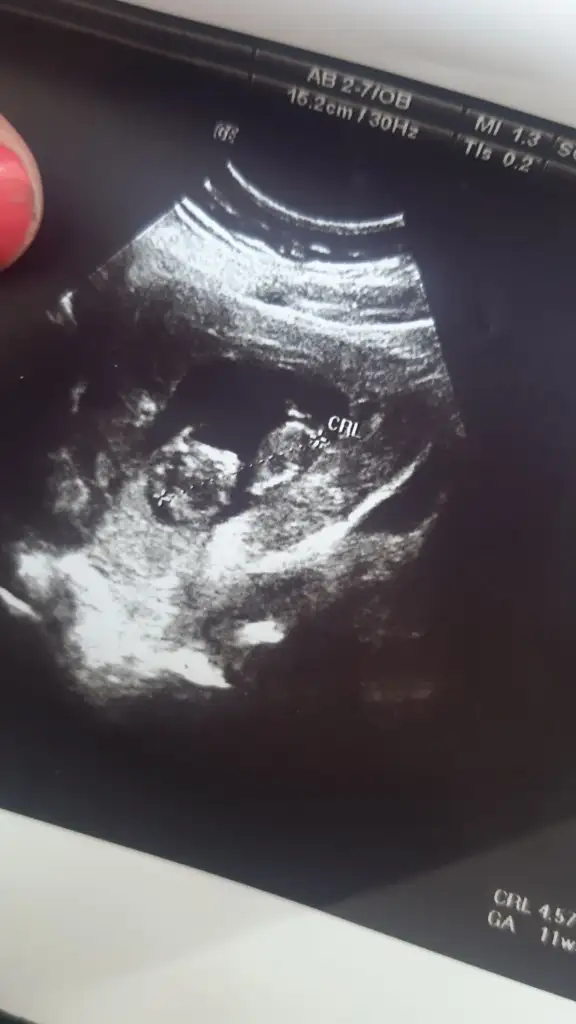

Daha önce ne dedim nub göremedim 12-13 hafta olursa paylasinIkra meyra tahmim alabilir miyim bugün 11 haftalık olduk

Daha önce bir şey dememiştiniz . Benim de adete göre 11 ultrasona göre 11+3 artık bir sonraki haftaya o zmanDaha önce ne dedim nub göremedim 12-13 hafta olursa paylasin

Erkek gibi sanki nette değil olmayada bilirMerhaba , bugün ki usg 11+6 günlük tahminde bulunabilir mısınız?![]()